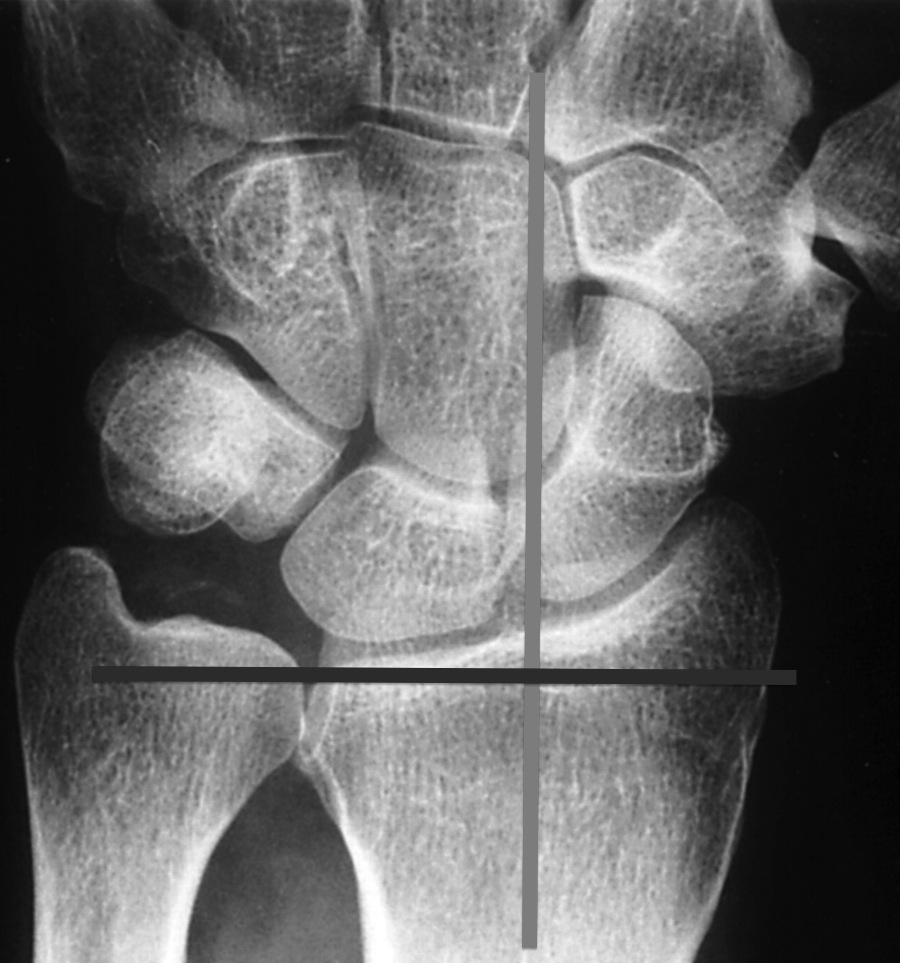

Method of Perpendiculars - draw line along long axis of the radius (light line). draw line perpendicular to this, through the ulnar corner of the radius (dark line).

how to draw the ulnar variance